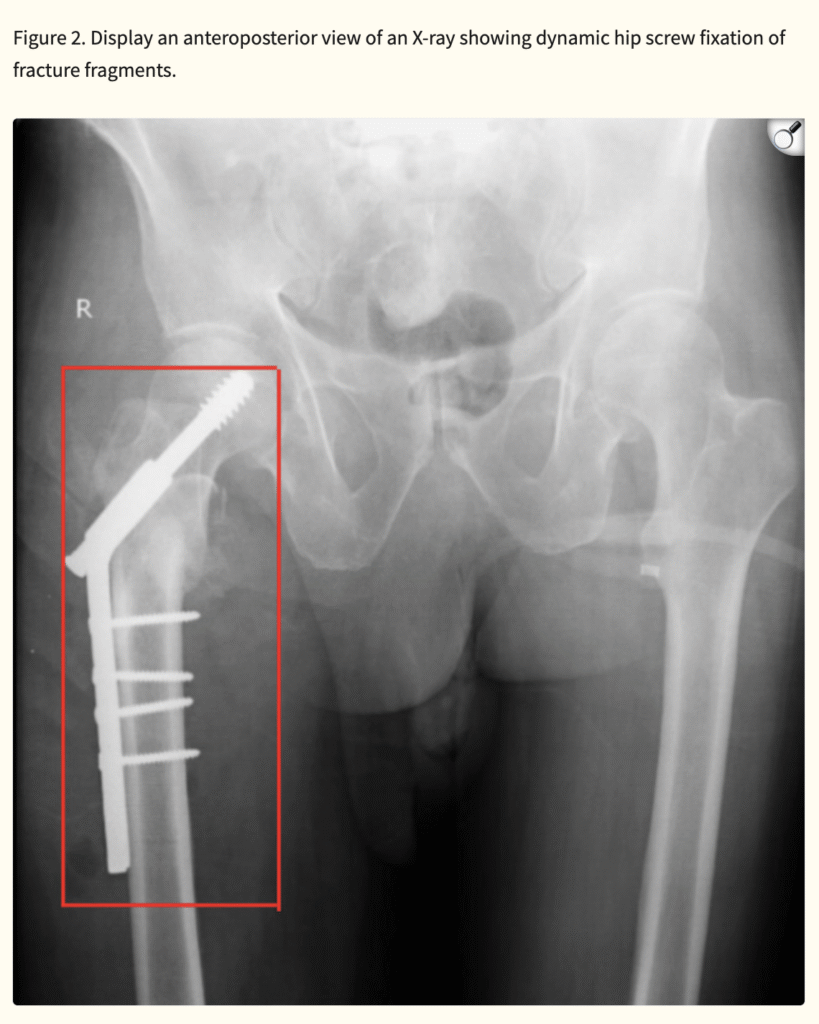

Intertrochanteric fractures are increasingly prevalent as life expectancy rises worldwide. Osteoporosis and accidental falls remain the leading risk factors among older adults. While surgical stabilization is the treatment of choice, complications such as infection, non-union, avascular necrosis, venous thrombosis, and post-traumatic arthritis may hinder recovery.

Even with surgical intervention, nearly half of patients fail to regain pre-injury mobility. Thus, rehabilitation plays a pivotal role in restoring function, maintaining independence, and preventing long-term disability. Early stabilization of hip fractures allows for quicker mobilization, shorter hospital stays, and reduced complications, ultimately improving survival and quality of life.

Physiotherapy contributes substantially to recovery by addressing pain, swelling, joint stiffness, muscle weakness, impaired coordination, and balance deficits. Progressive strengthening, gait training, and functional retraining help patients regain mobility and confidence, reducing the risk of recurrent falls.